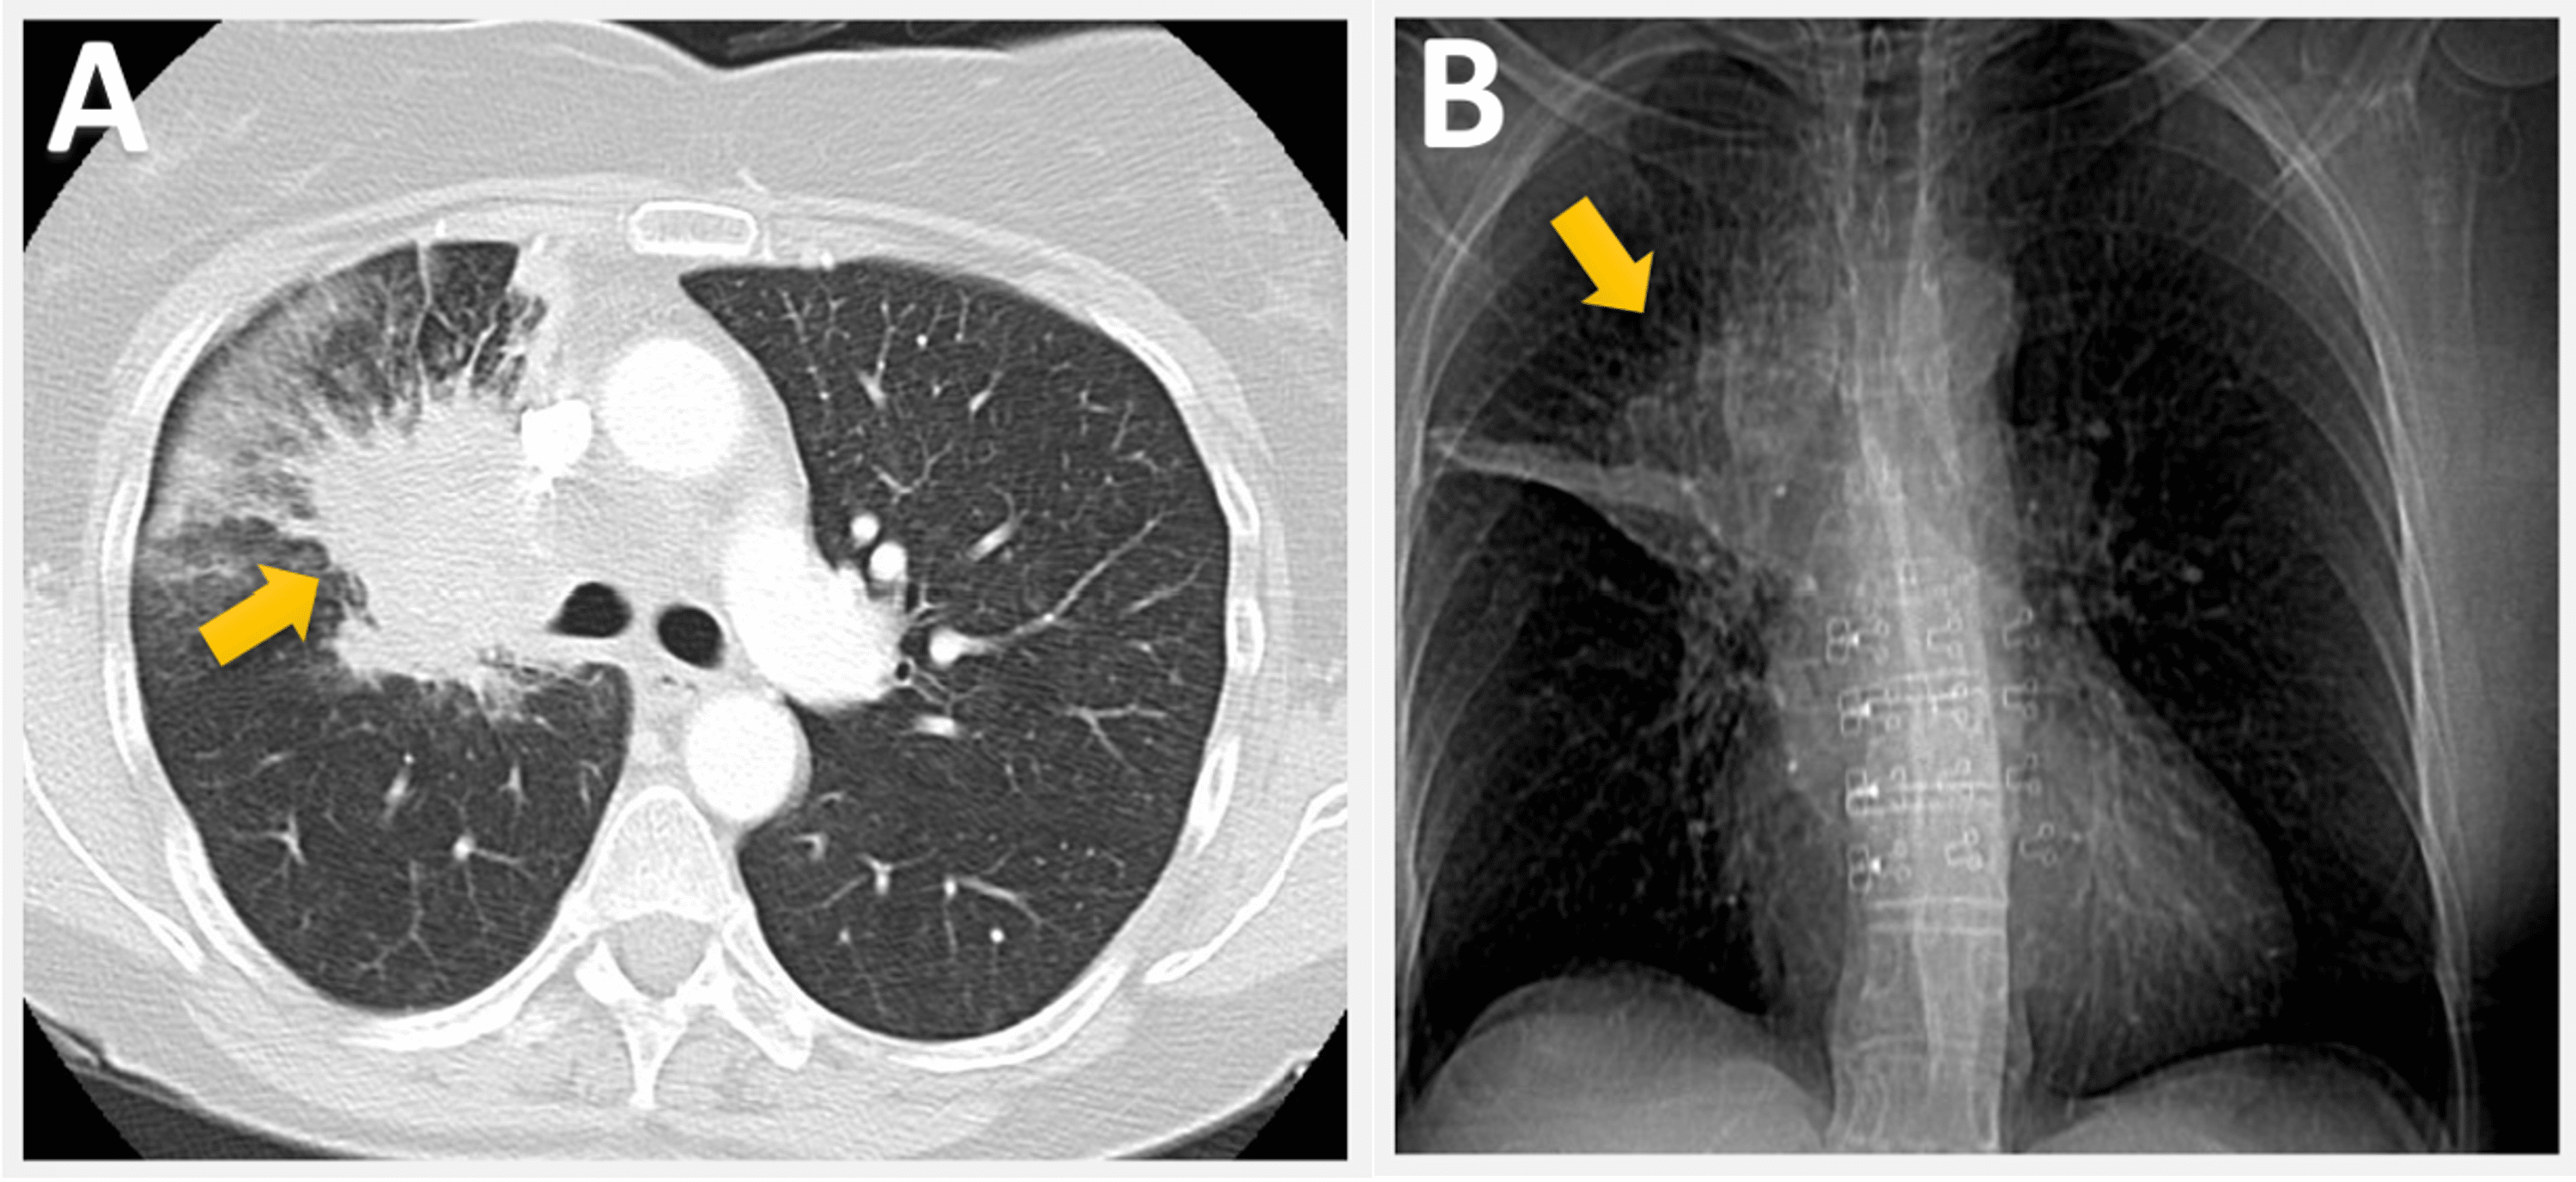

Computed tomography scan of the chest showed 2.1×2.5 cm spiculated mass

Computed tomography scan of the chest showed 2.1×2.5 cm spiculated mass Spiculated Left Upper Lobe Mass they removed a 3.1cm mass from my upper right lung (stage 1b not 1a because of size). spiculation of the nodule anatomical margins has been persistently shown to correlate with an increased risk. both lesions in the right upper and middle lobe showed a suspicious. a solitary pulmonary nodule is a discrete lesion < 3 cm. Spiculated Left Upper Lobe Mass.